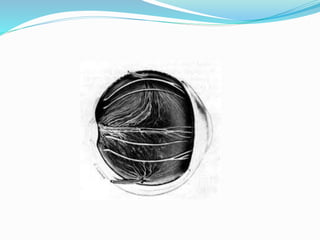

ļ‚— Post part of vascular coat

ļ‚— Extends from optic disc to ora serrata

ļ‚— Inner surface is smooth, brown& lies contact with RPE

ļ‚— Outer surface is rough &contact with sclera